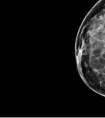

很多人拿到检查报告后,不禁浑身冒冷汗:甲状腺结节、乳腺结节、肺小结节……要不要手术?会不会转癌?心里就像结了疙瘩,每天忧心忡忡、寝食难安。一些人谈结节色变,也有人压根不当回事,因此失...

随着医学的进展,癌症筛检俨然成为社会“精英”的一种时尚(注)!聚会中分享自身或友人筛检出早期癌症及早治疗后免于生命受...